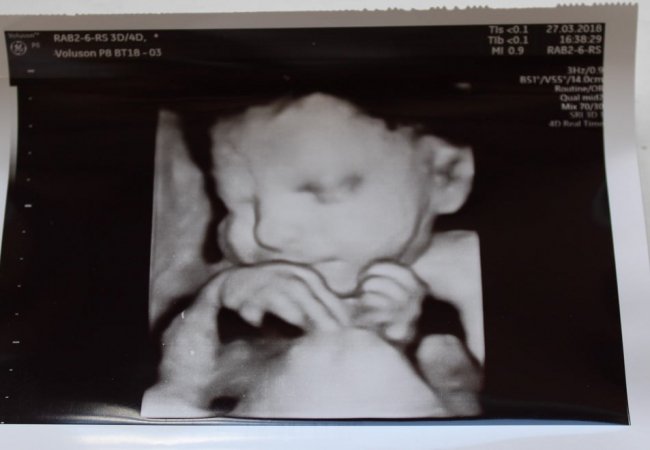

У пологовому будинку Ковельського МТМО на УЗД-апараті роблять чіткі фото дитини ще до його народження.

Інформують, що у жіночій консультації працює УЗД-апарат нового покоління з додатковим набором функцій, який дає найвищу якість зображення і демонструє найновіші можливості діагностики в акушерстві і гінекології, має високий рівень візуалізації, включаючи можливості 3D/4D. Таке ультразвукове дослідження є абсолютно безпечним як для вагітної жінки, так і для плоду.

Для майбутніх батьків – це не лише можливість точно дізнатися стать свого малюка, на появу якого вони очікують, а й розгледіти риси його обличчя та з’ясувати, на кого він буде подібний. В режимі 4-D, тобто в реальному часі, можна побачити рухи малюка, його посмішку. А за допомогою технології 3D-друку можна отримати кольорову світлину - точну тривимірну копію майбутнього малюка.

Для лікарів-акушерів такий метод діагностики дозволяє побачити плід в об'ємі. Спеціальні датчики та програмне забезпечення є хорошими інструментами для додаткової оцінки вроджених вад розвитку, які характеризуються хромосомними аномаліями. Сучасна технологія високоякісного панорамного зображення дозволяє реконструювати площини, які не доступні при звичайному 2D-режимі УЗД. Зокрема, для діагностики патологій нервової системи, хребта та кінцівок, обличчя плоду.